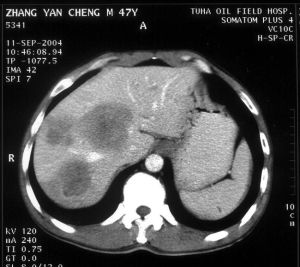

1.影像學技術的發展:包括更清晰的數字X光片、CT、MRI、ECT等技術臨床上獲得了廣泛套用